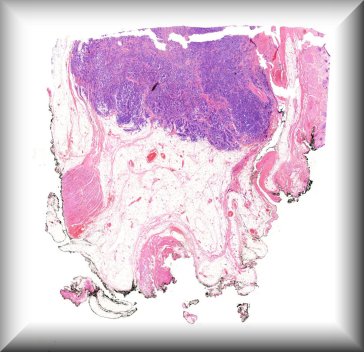

Fiona Roberts (Glasgow): 9 year old female with buphthalmos secondary to congential glaucoma. Protocol |